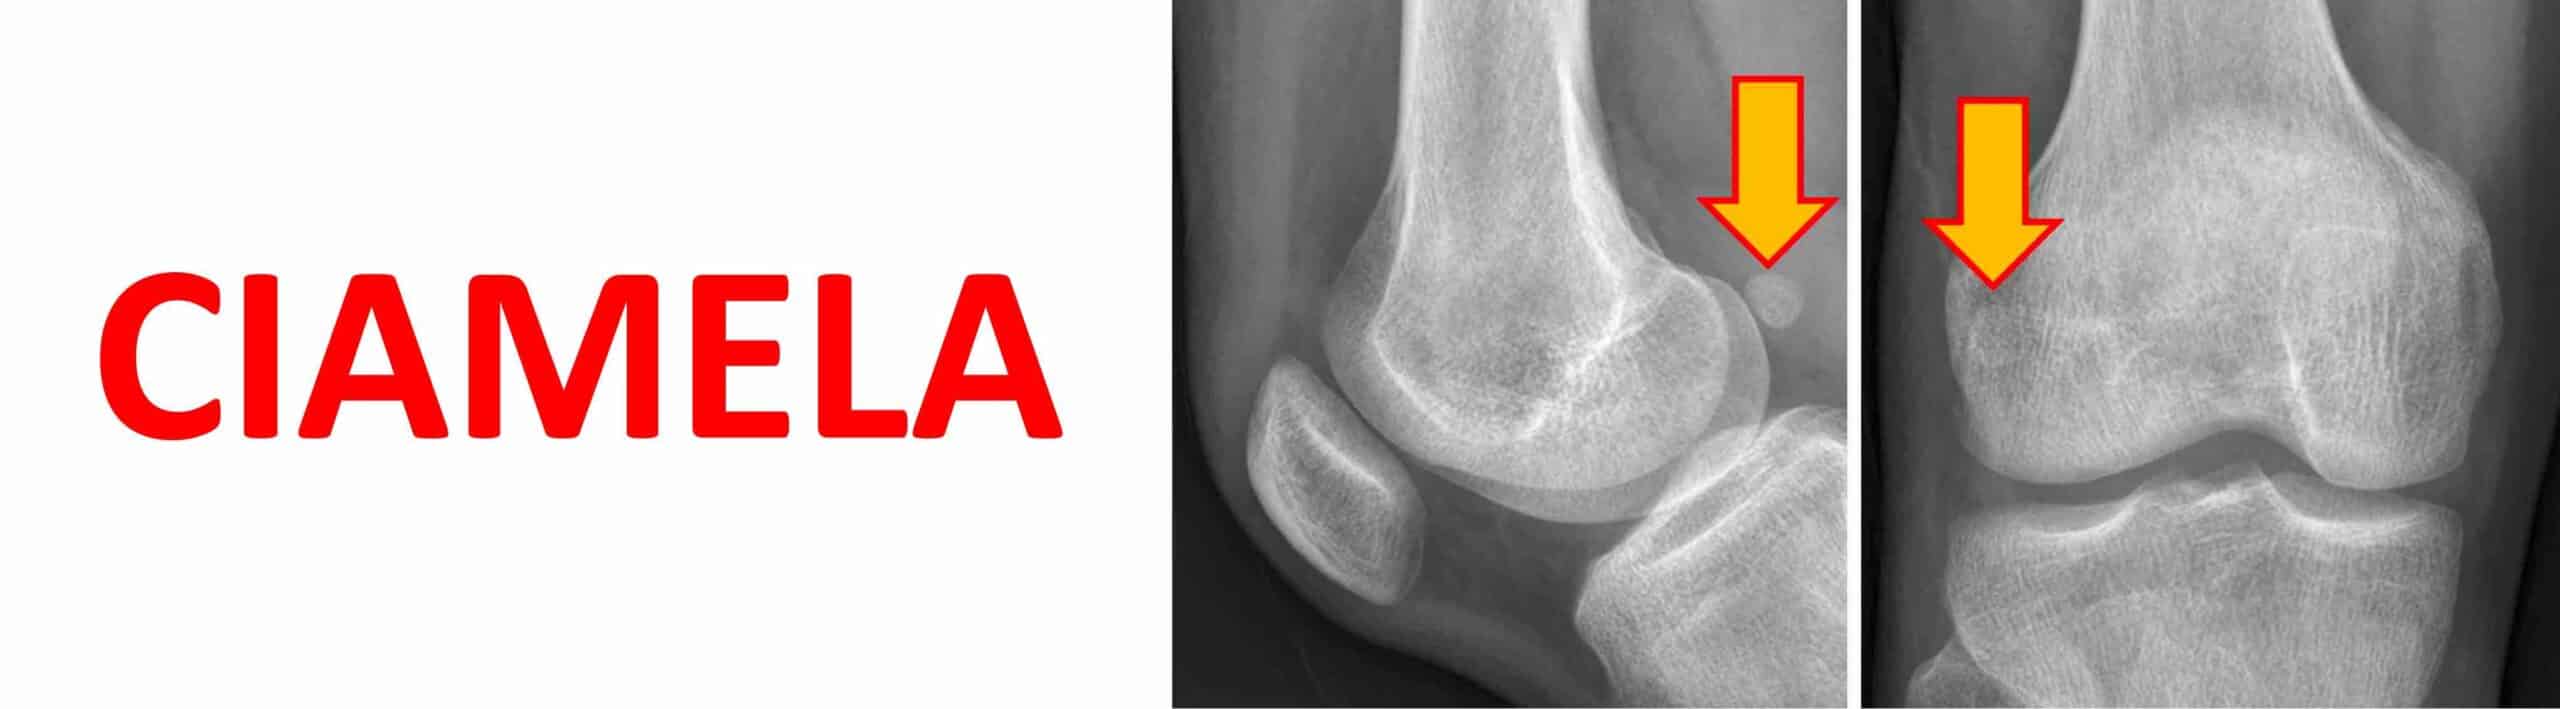

CIAMELA

A ciamela é um osso sesamóide do joelho ainda mais raro do que a fabela. Ela também fica localizada na região posterior do joelho, dentro do tendão do músculo poplíteo. A presença da ciamela no joelho é extremamente incomum em humanos. A sua presença no joelho costuma ser assintomática. Pode, eventualmente, ser a causa de dor na região posterior e lateral do joelho, especialmente em atletas. Saber da sua existência é importante para que ela não seja confundida com um fragmento ósseo ou corpo livre intra-articular. Isso pode acontecer porque o tendão do músculo poplíteo é intra-articular, ou seja, a ciamela, quando presente, costuma estar localizada dentro do espaço articular do joelho.